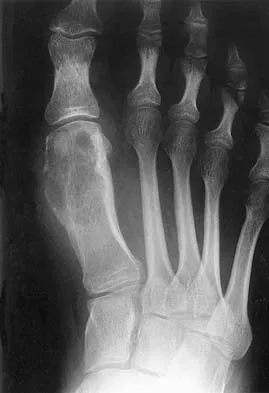

The oblique radiograph of the foot and the CT scan shown in Figures 10a and 10b show a patient whose symptoms have failed to respond to rest and non-steroidal anti-inflammatory drugs. What is the best course of action?

The radiograph and MRI scan show elongation and fragmentation of the os peroneum. Although casting, orthoses, and steroid injection may relieve symptoms, excision of the os peroneum and primary repair when necessary, with or without tenodesis of the peroneus longus to the peroneus brevis, have been shown to produce excellent results. Haddad SL: Disorders of tendons: Peroneal tendon dysfunction, in Coughlin MJ, Mann RA (eds): Surgery of the Foot and Ankle, ed 7. St Louis, MO, Mosby, 1999, pp 812-817.